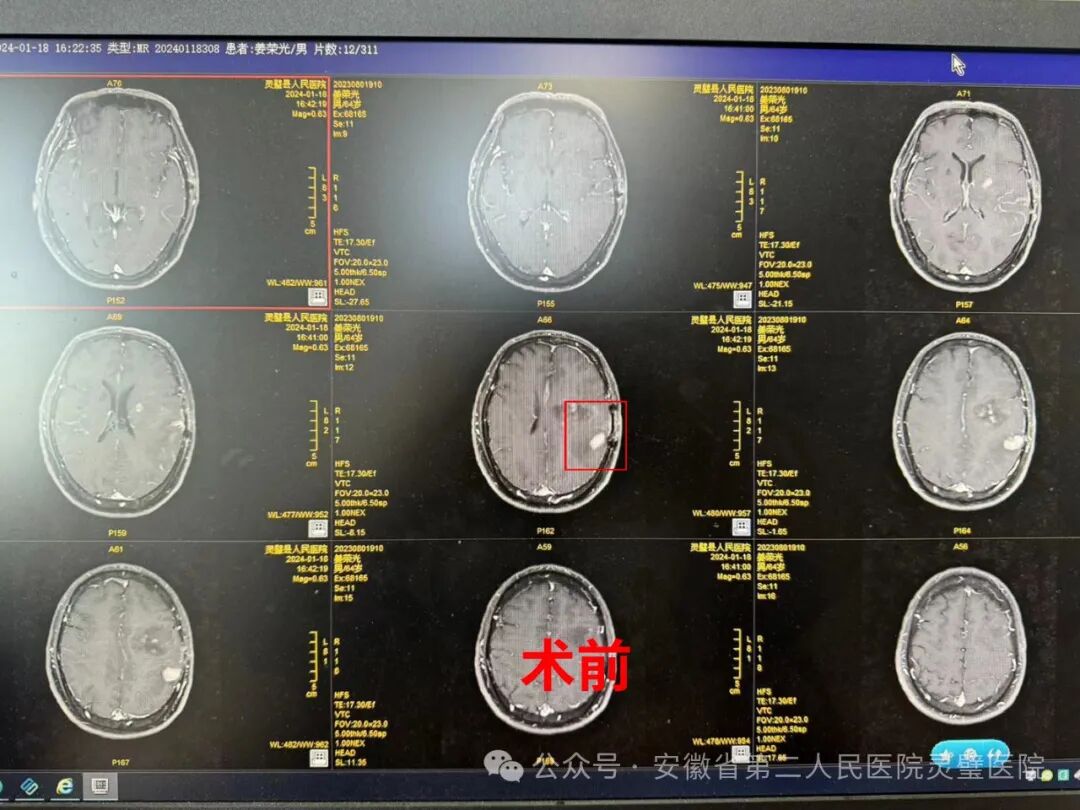

患者男,65岁,外院颅内占位性病变术后半年余,现因右侧肢体无力麻木入院,头颅磁共振及CT检查显示左侧额顶叶占位,已至右侧肢体麻木、混合型失语。如不处理,将进一步增大造成更严重的后果甚至危及生命。排除手术禁忌症,做好术前准备后,神经外科张永明主任、魏山主任在显微镜下开颅行左侧颞叶占位切除术。术中见左侧颞叶胶质瘤约2cm,显微镜下将颞叶胶质瘤完整切除,术中出血约20ml,手术圆满成功,麻醉清醒后安返病房。术后复查CT,占位完全切除,目前恢复良好,无神经功能缺失。